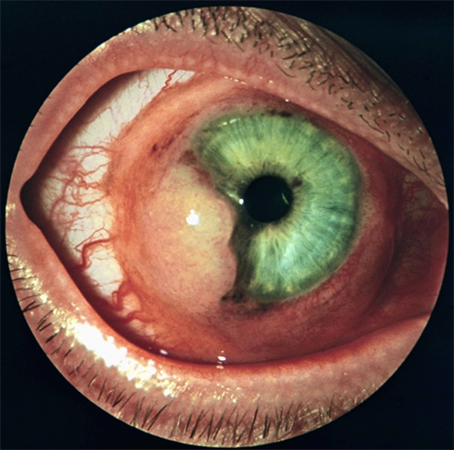

Когда глаза поражены, пациенты отмечают ухудшение зрения, ощущение давления в области глаз, нарушение функции хрусталика, отслаивание сетчатки, снижение зрительной функции до полной слепоты, а также возможное появление следующих симптомов:

- Сосудистая оболочка глаза становится воспаленной, что приводит к отеку слизистой оболочки.

- Возникает ощущение жжения в глазах.

- Увеличивается количество слез, наблюдается повышенное слезотечение.

- Происходит воспаление сетчатки глаза.

- Появляется конъюнктивит.

В любом случае цистицерки приводят к уменьшению размеров глазного яблока. Отдельные паразиты, обитающие в глазах и мозге, удаляются при помощи операции.